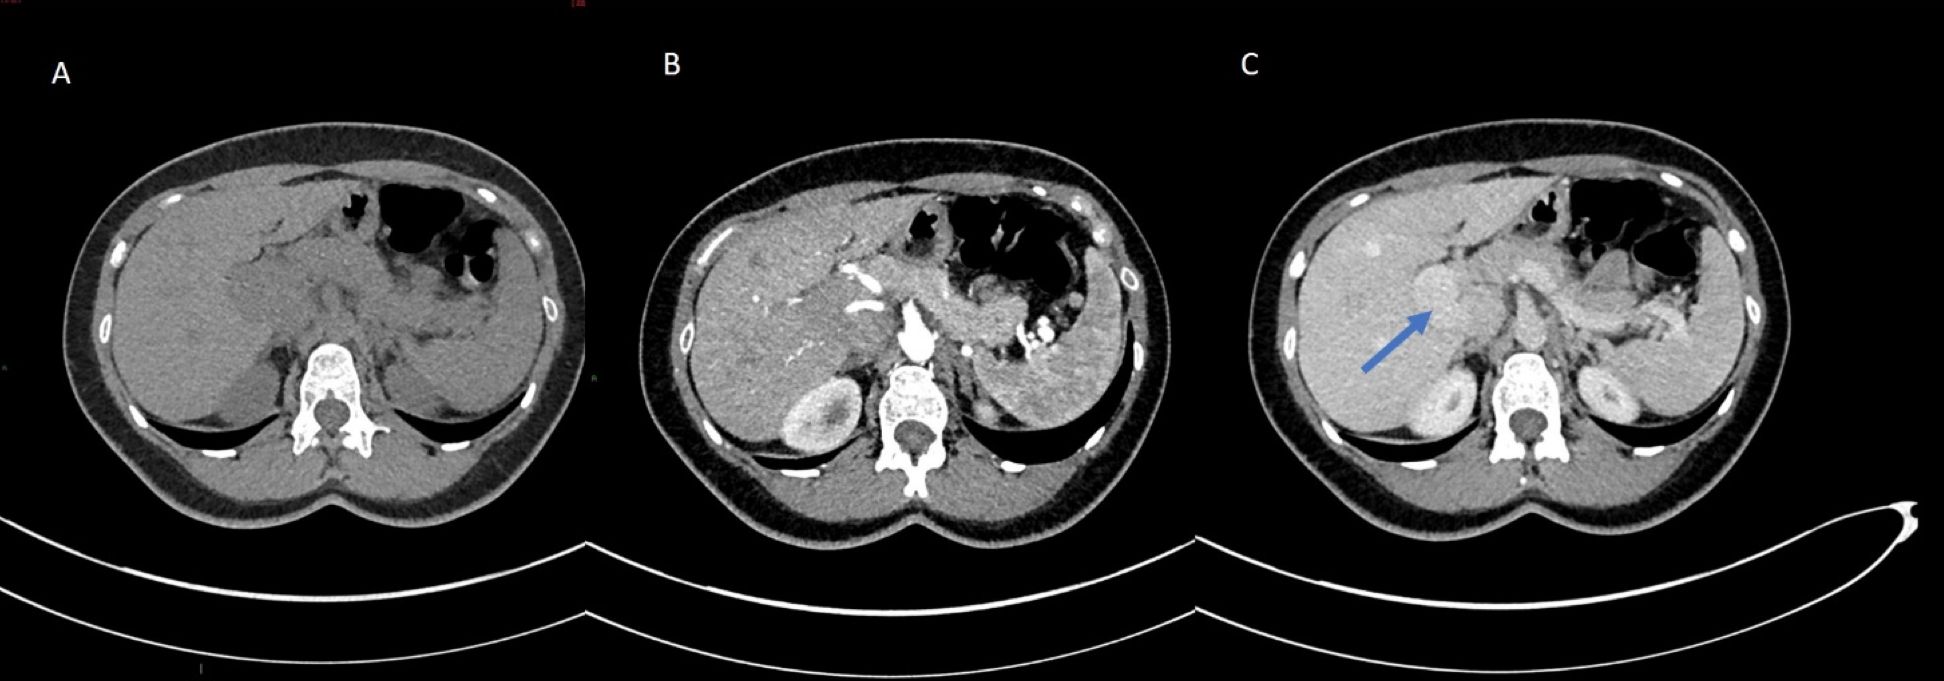

Based upon the MRI findings, she was investigated for any underlying causes of elevated manganese. On abdominal ultrasound, the liver had a normal size, outline, and echotexture. Interestingly, the right branch of the portal vein appeared to drain directly into the inferior vena cava. A congenital porto-systemic shunt was confirmed on a triple phase CT study of the liver which proved that the right branch of the portal vein drained directly into the IVC. There were no features to suggest chronic liver disease or collateralisation of the vessels.